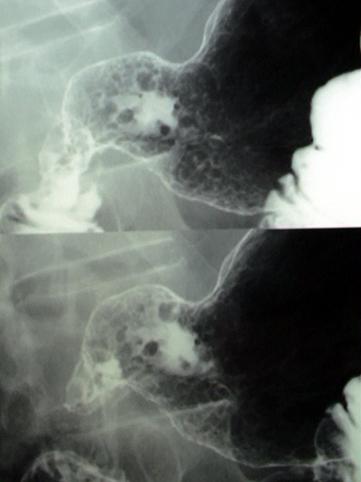

clasificación del pacienteTumor Maligno del Sistema Linfático/Linfoma Maligno

parte(separada por órganos)estómago(región)/antro

método de exámenRayos X

clasificación ectoscópica de tumoresTipo 0(tipo superficial)/Tipo IIc(IIc)

diámetro mayor del tumor40 -

grado de penetraciónsm